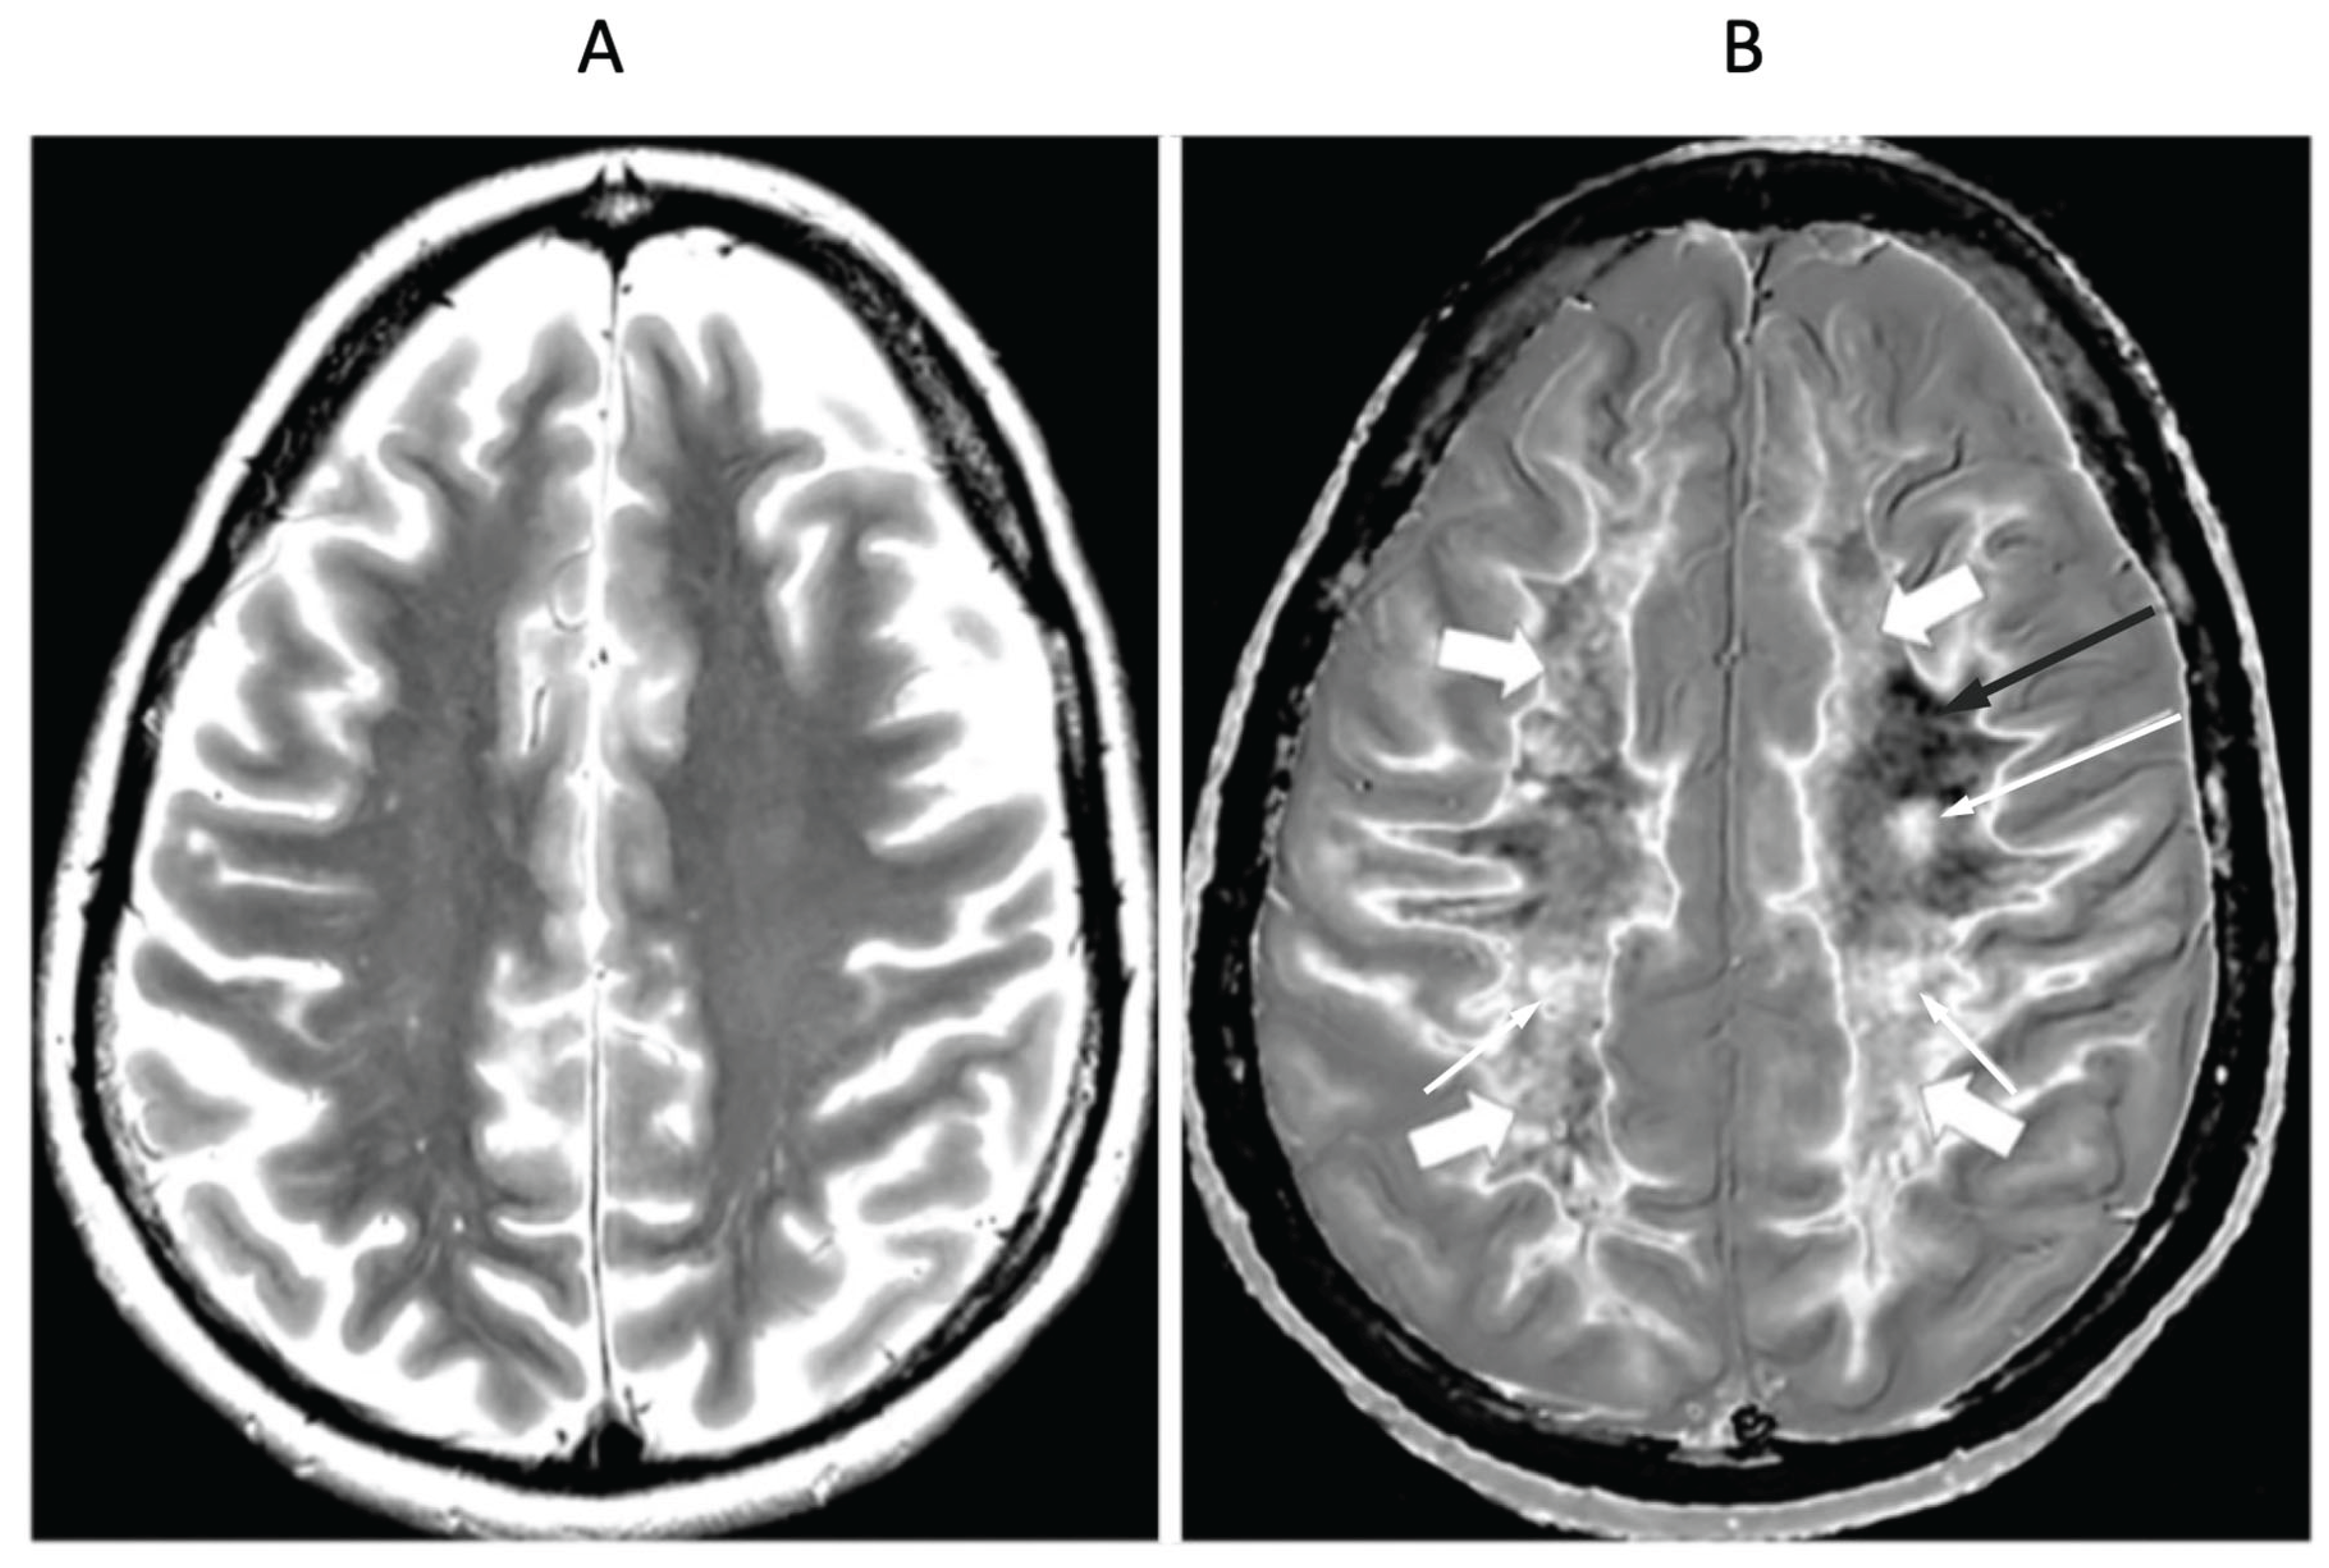

- Mild Traumatic Brain Injury (mTBI)

- Multiple Sclerosis (MS)

- Condron, P.; Cornfeld, D.M.; Scadeng, M.; Melzer, T.R.; Newburn, G.; Bydder, M.; Kwon, E.E.; McGeown, J.P.; Handsfield, G.G.; Emsden, T.; et al. Ultra-High Contrast MRI: The Whiteout Sign Shown with Divided Subtracted Inversion Recovery (dSIR) Sequences in Post-Insult Leukoencephalopathy Syndromes (PILS). Tomography 2024, 10, 983–1013. [Google Scholar] [CrossRef] [PubMed]

- Newburn, G.; McGeown, J.P.; Kwon, E.; Tayebi, M.; Condron, P.; Emsden, T.; Holdsworth, S.J.; Cornfeld, D.M.; Bydder, G.M. Targeted MRI (tMRI) of Small Increases in the T1 of Normal Appearing White Matter in Mild Traumatic Brain Injury (mTBI) Using a Divided Subtracted Inversion Recovery (dSIR) Sequence. OBM Neurobiol. 2023, 07, 1–27. [Google Scholar] [CrossRef]